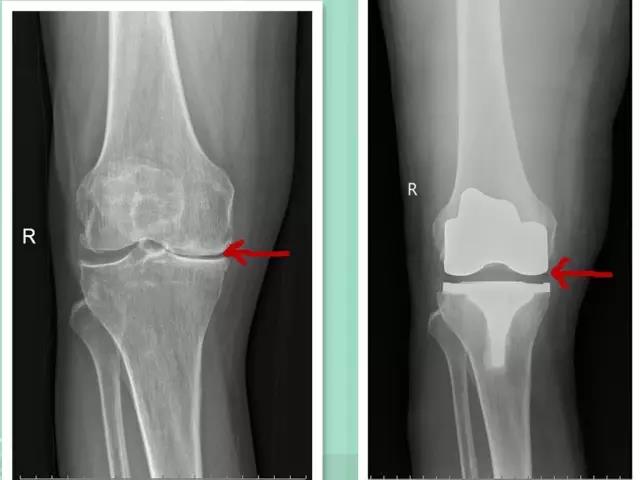

自从杜女士退休后,她的两条腿也跟着*工罢**了,别说是上下楼梯,就连平时走路都比别人费好大劲。膝盖像被针扎一样,传来阵阵钻心的疼痛。于是她只能待在家里。杜女士本来以为少走路就能减轻疼痛,可是腿疼的情况并没有得到缓解,而是在一天天加重,最后甚至到了难以下地的程度。就这样她不得不来到医院寻求医生的帮助。当时接诊的医生为她做了初步的检查,发现她的腿已经变形,而且无法像正常人那样自由地弯曲,已经严重影响到了日常生活。为了对杜女士的病情有更直观的了解,医生建议她去拍个X线摄影,当检查结果出来之后,在场的医生们都为之一惊。

杜女士主要是膝关节内部产生大量的增生,内翻,而且伴脱位。这是老年热最常见的骨病,叫做骨性关节炎。很多人经常拖着不治,其实到医院做个X线摄影,即可确诊。

晚期骨性关节炎患者可选择人工关节置换

膝关节置换手术,是在对患者实施全身麻醉的情况下,在膝盖处做一个切口,将髌骨切除,并且把股骨和胫骨上面的骨刺和粗糙的地方刮除,然后置入人工关节,用特殊的骨水泥将假关节套牢在骨头表面。术后患者经过几周的康复便能行动自如。